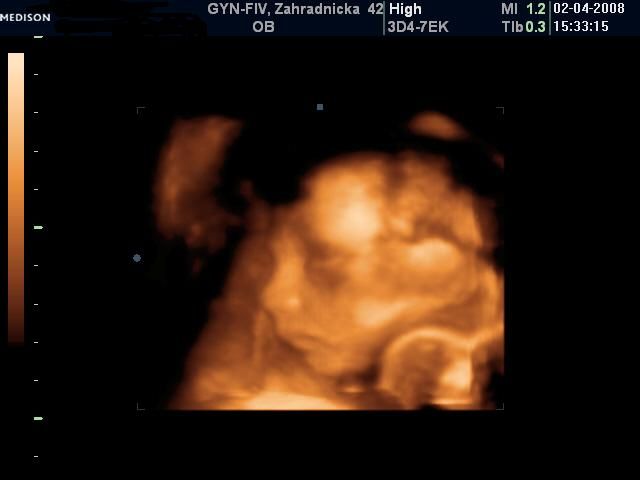

Bol to krásny deň napriek upršanému počasiu (aspoň sme sa nepotili) ;-) Všetci ma utešovali, že to nám prší šťastie a ja tomu verím.